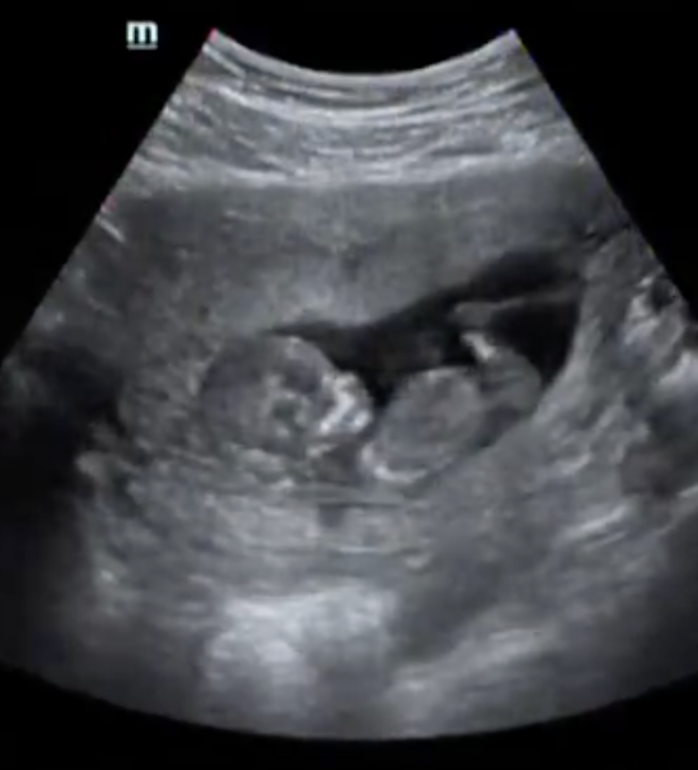

Эксперты по бугоркам - ау :)

Были сегодня на скрининге с крохой, врач на 65 процентов предположил пол :) Скоро будет НИПТ, проверим :)

Как вы думаете, мальчик или девочка? (фото подкат)

Бугорок ну прям сразу же видно , что девчачий , мальчика тут , нуу никак нельзя было увидеть.

Девочка. У моего мальчика бугорок под углом 90° торчал, здесь параллельно позвоночнику.

Думаю девочка) у нас в этот раз прям торчал к верху)))я сразу подумала что как то впервые вижу такое🤭😁

Ну по бугорку я бы сказала что девочка.. Но я не верю уже в эти бугорки, процент ошибки велик. У нас был чётко вверх, но беременна девочкой)